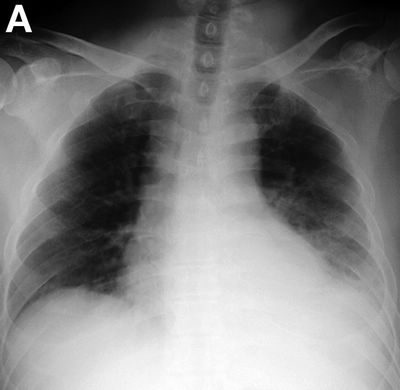

胸腔积液x线胸片报告,胸腔积液x线胸片图解

胸部超声提示左侧胸腔积液. 胸部增强ct结果如图b所示.

左侧胸腔积液 c.左侧液气胸 d.左侧肺不张 e.以上都不对

胸片(70岁,男,咳嗽,气喘,发烧,胸腔积液)

右肺胸膜肥厚 b.右肺不张 c.右侧胸腔积液 d.右肺炎症 e.右肺肺栓塞